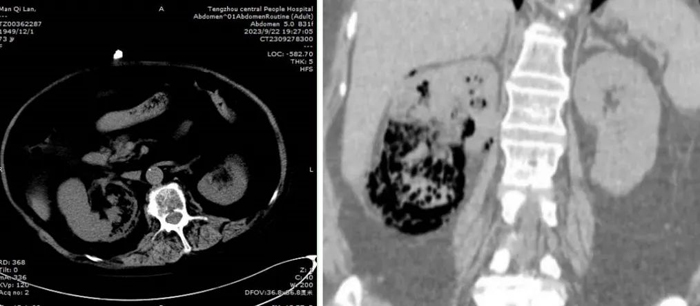

CT顯示右腎實質(zhì)積氣

滿阿姨轉(zhuǎn)入泌尿外二科后,單鋒芝副主任醫(yī)師組織科室討論,認(rèn)為患者有長期服用糖皮質(zhì)激素,免疫力下降等誘發(fā)本病的危險因素,經(jīng)CT檢查,診斷“氣腫性腎盂腎炎”成立,明確治療方案為抗菌素+內(nèi)置輸尿管支架引流+腎穿刺造瘺治療。